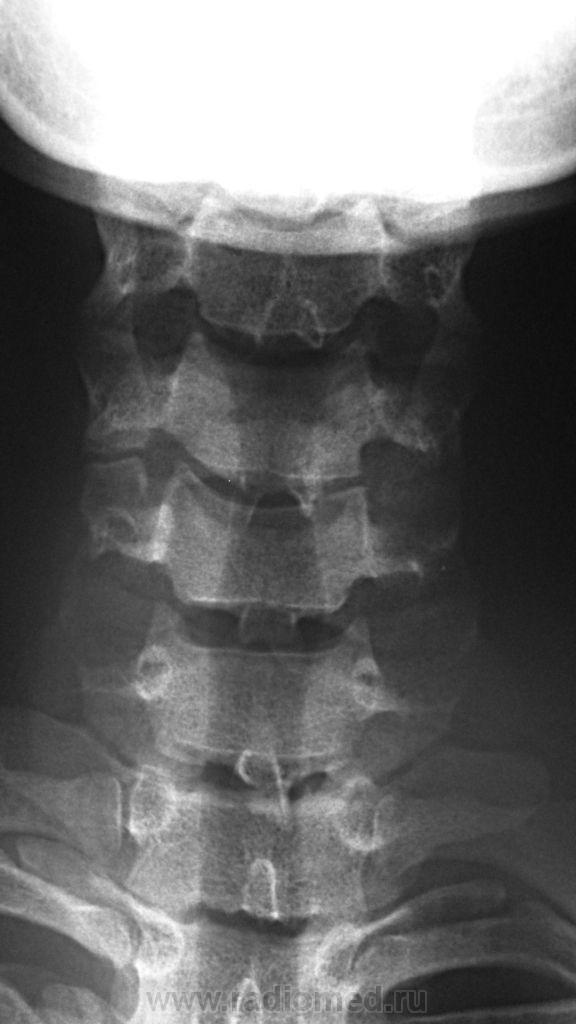

Дело в том, что именнов этом ПДС, определяется фиксация и ограничение объёма движений. Как видите - ни при згибании, ни при разгибании ширина и форма межпозвонкового диска не изменяется. Да и форма тела С5 мне кажется весьма отличной от других тел... Такое впечвтление, что сформирован неоартроз.

Там действительно есть неоартроз с деф артрозом, но  это точно не сами позвонки, а части избыточно развитых отростков...

Спасибо Анатолий Иванович, понял что это гиперплазированные поперечные отростки тел С5 и С6, с сформированым между ними неартрозом и деф. артрозом. Вообще эта пациентка какаято странная - жалуется на похудение одной (правой) половины тела. Напрвляли её на ПКОП - ничего кроме сколиоза, с небольшим торсионным компонентом нет. Тут вот шейный отдел, надо бы грудной снять, а тут опять кто то из врачей сказал, что много уже рентгена и на грудной не направили...